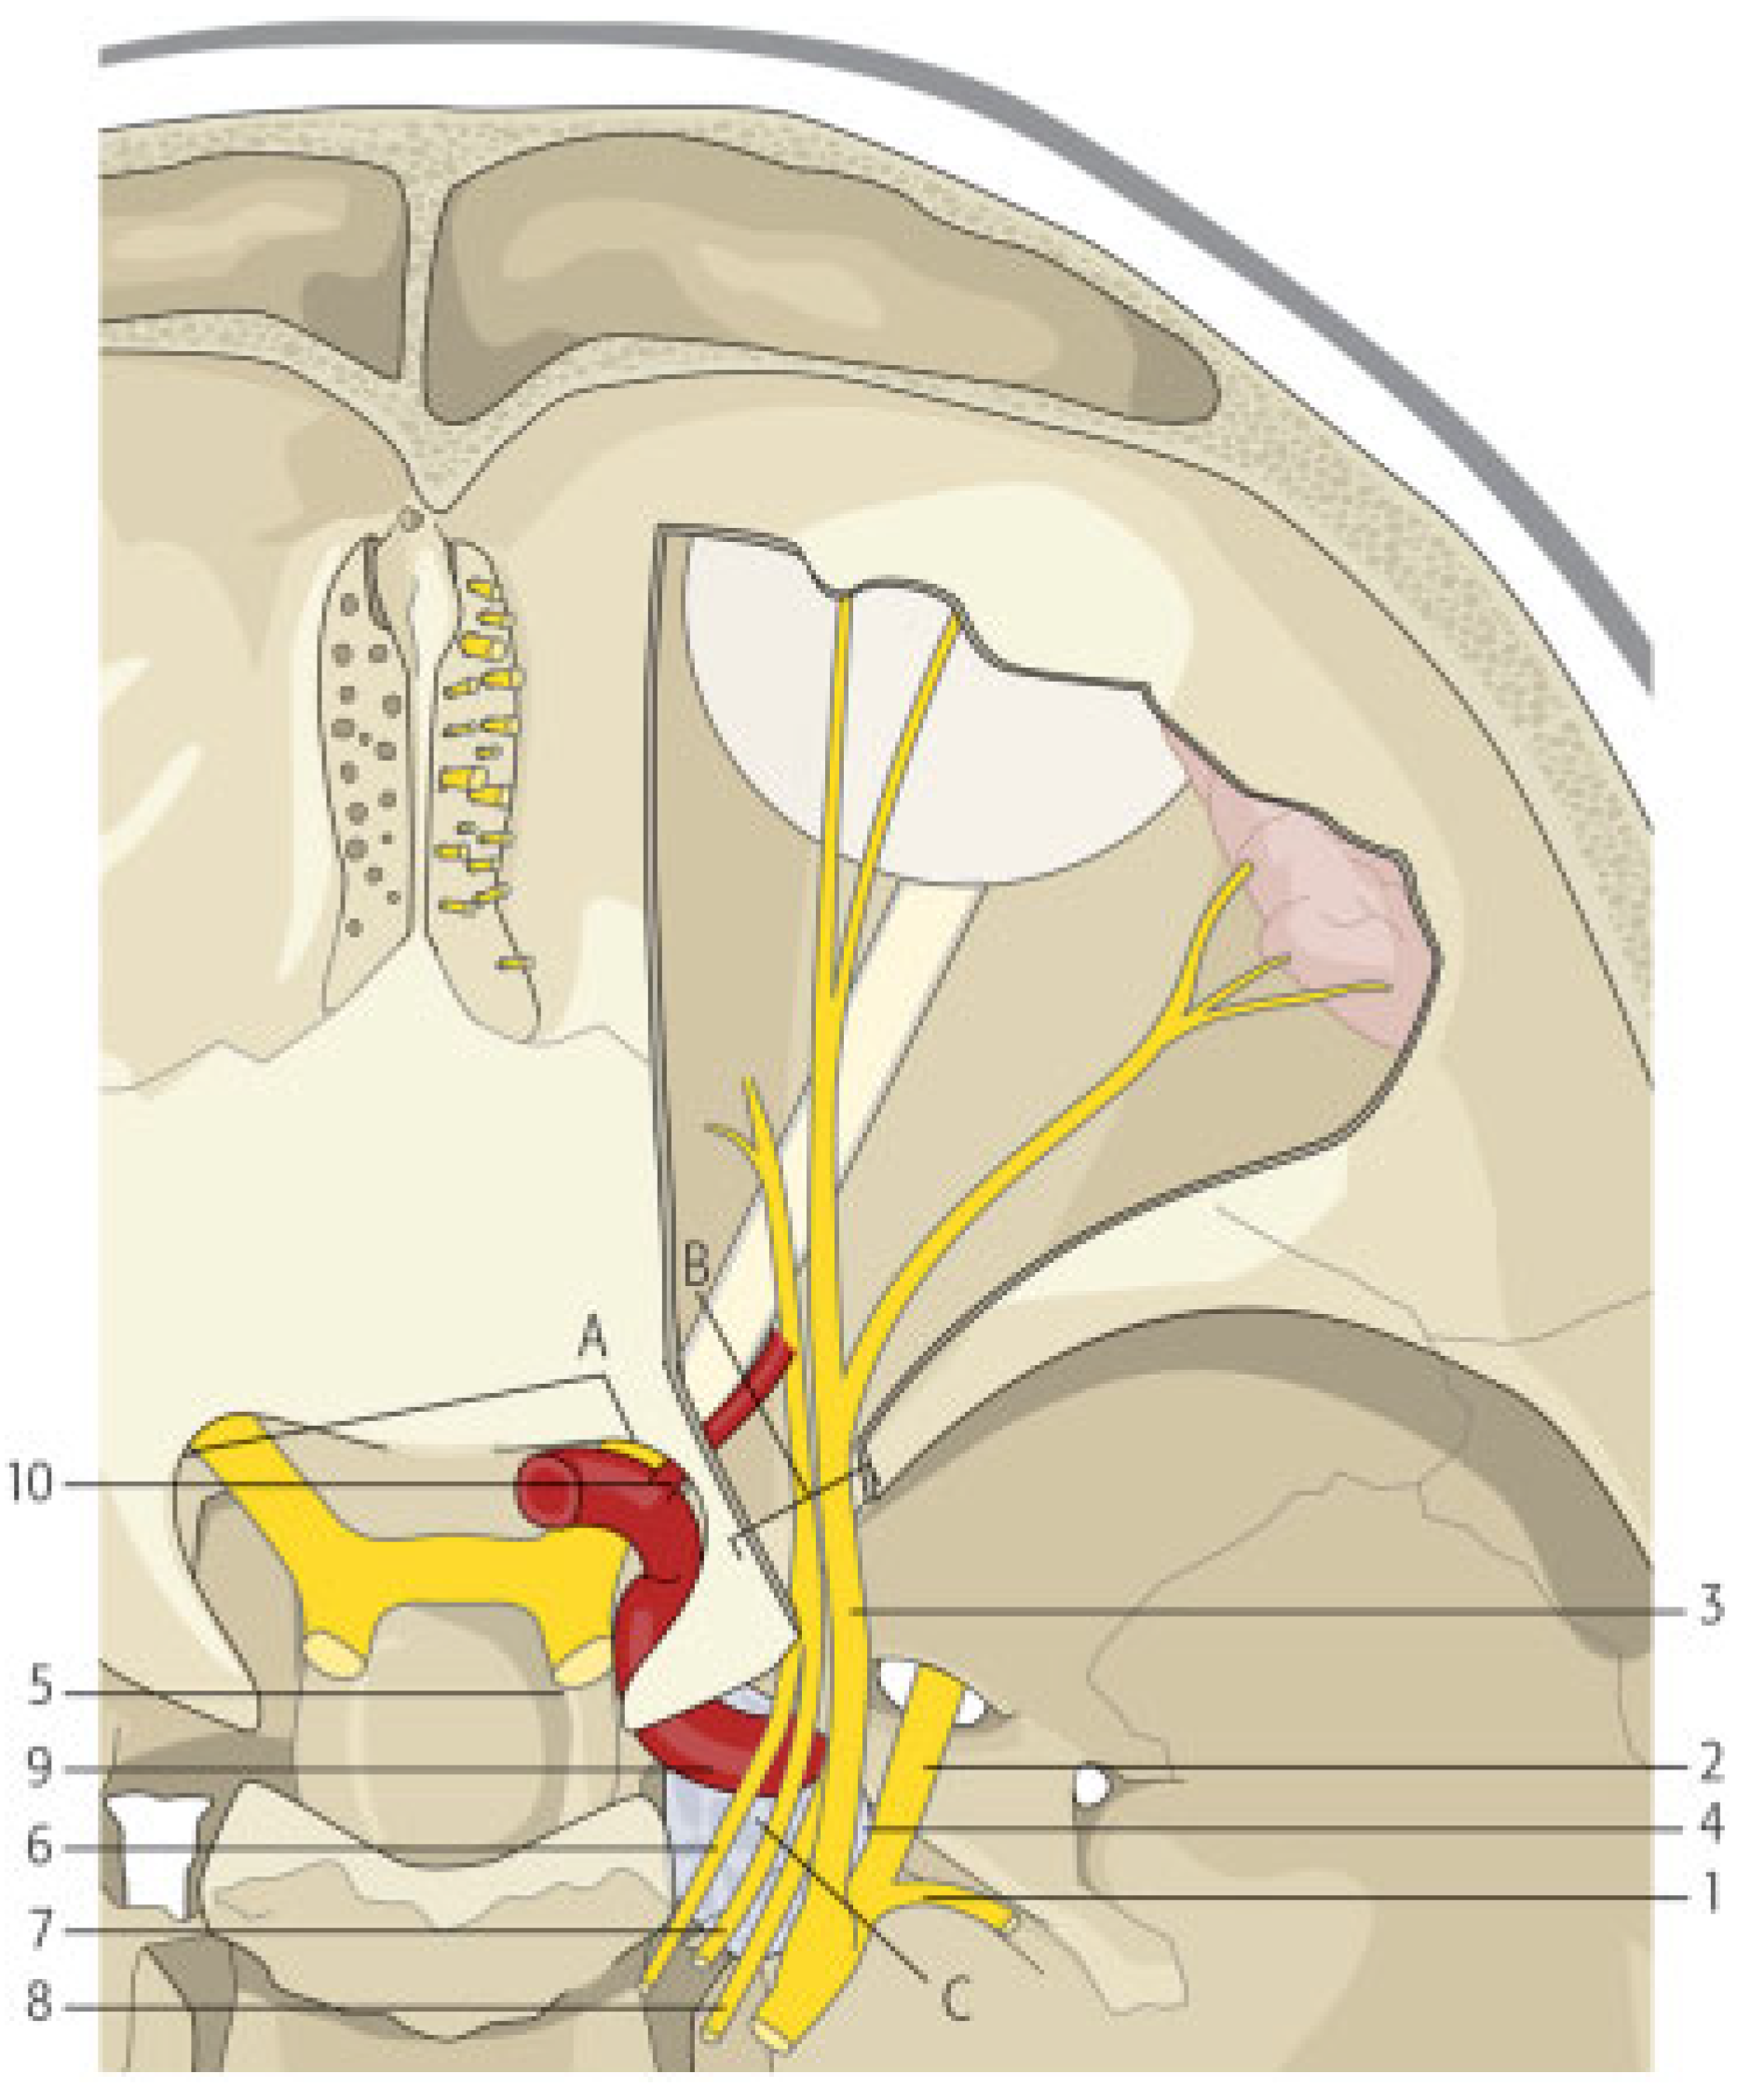

The clinical picture is explained by the sudden increase of the blood pressure in the cavernous sinus that leads to impaired drainage of structures that are normally drained by cavernous sinuses and increased pressure on structures that traverse the sinuses [1]. The cavernous sinuses are paired structures that are composed of multiple venous sinusoids. They receive blood from superior and inferior ophthalmic veins, pterygoid plexus, sphenoparietal sinuses, and superficial cerebral veins. Through these blood filled spaces pass the internal carotid artery and cranial nerves III (oculomotor), IV (trochlear), V1 (ophthalmic division of trigeminal nerve), V2 (the maxillary division of the trigeminal nerve), and VI (abducens). All these cranial nerves, except from VI, pass through the lateral wall of the sinus, while the cranial nerve VI passes through the middle of the sinus alongside the internal carotid artery.

Differential diagnosis is difficult because various pathologic entities present with similar symptoms. It includes the superior orbital fissure syndrome, orbital apex syndrome, retrobulbar hematoma, and cavernous sinus syndrome [17] (Table 2). In fact, the superior orbital fissure, the orbital apex, and the cavernous sinus are contiguous anatomical structures that may be affected by similar causes such as traumatic, inflammatory, neoplastic, and vascular (Figure 6 and Figure 7). Consequently, a broad category of diseases can cause the so-called superior orbital syndrome or the orbital apex syndrome or the cavernous sinus syndrome. Posttraumatic CCF is basically a vascular cause of the cavernous sinus syndrome. The symptoms of all the earlier-mentioned syndromes are similar because almost the same cranial nerves are involved, but there are some differences that help establishing the exact diagnosis. In the case of the superior orbital fissure syndrome, the patient may present with ophthalmoplegia, diplopia, hypesthesia in the distribution of V1, upper lid ptosis, exophthalmos and fixation, and dilatation of the pupil. If the orbital apex (orbital apex syndrome) is also involved, visual loss is also added to the clinical picture. If the cavernous sinus is involved (cavernous sinus syndrome), the clinical manifestations may involve the features of the superior orbital fissure syndrome with the added involvement of the maxillary branch of trigeminal nerve (V2) and oculosympathetic fibers [18]. When the cavernous sinus syndrome is caused by a CCF, all these symptoms may be present. Moreover, pulsatile exophthalmos is usually present, a clear systolic wheeze is typically heard on auscultation of the orbital region, the patient usually complains of “strange noises in the head” and the intraocular pressure may be elevated. When these symptoms and signs are present in a patient with a history of craniomaxillofacial trauma, post- traumatic CCF must be suspected. In the case presented, diagnosis of posttraumatic carotid aneurysm initially and CCF later was difficult for two reasons. The first reason was the associated facial fractures of the zygomatic complex, nasal bones, and orbital floor which cause similar findings and led to the first false diagnosis of posttraumatic superior orbital fissure syndrome. Second, the osteosynthetic and alloplastic material that were used around the left eye led to the other false diagnosis of postoperative infection-orbital cellulitis. The persistent clinical signs and their deterioration despite removal of foreign materials and intravenous antibiotics led to the right diagnosis of CCF. However, a high index of suspicion and a deep knowledge of this pathologic entity would probably lead to the right diagnosis from the beginning, if auscultation of the orbital region had been performed.

Figure 6. (a) Schematic drawing showing which structures pass through the cavernous sinus and are consequently affected in case of cavernous sinus syndrome or carotidcavernous fistula (1) oculomotor nerve, (2) trochlear nerve, (3) ophthalmic division of trigeminal nerve, (4) maxillary division of trigeminal nerve, (5) abducens nerve, (6) internal carotid artery, (7) cavernous sinus, (8) pituitary, and (9) sinus sphenoidalis. (b) Schematic drawing showing the superior orbital fissure and the optic foramen together with the structures that pass through each of them. In case of a fracture that involves the superior orbital fissure, structures that pass through the fissure into the orbit are usually affected. If the optic foramen is also involved, the patient also suffers from loss of visual acuity due to mechanical compression of the optic nerve or the central ophthalmic artery. (1) lacrimal nerve, (2) frontal nerve, (3) superior ophthalmic vein, (4) trochlear nerve, (5) oculomotor nerve superior branch, (6) abducens nerve, (7) nasociliary nerve, (8) oculomotor nerve inferior branch, (9) inferior ophthalmic vein, (10) optic nerve, (11) ophthalmic artery, (A) superior orbital fissure, (B) optic foramen.

Figure 7. Schematic drawing showing the anatomic continuity of the cavernous sinus, the orbital apex, and the superior orbital fissure. Posttraumatically, each of these structures may be involved with similar clinical manifestations. Cranial nerves III, IV, VI, and V1 pass through both the cavernous sinus and the superior orbital fissure to enter the orbit. This is the reason why diplopia, ophthalmoplegia, ptosis of the upper lid, mydriasis, and frontal sensory loss are common manifestations. Maxillary division of the trigeminal nerve passes through the cavernous sinus but not through the superior orbital fissure. (It exits the cranium through foramen rotundum). This is the reason why sensory loss of infraorbital area, nose, and upper lip is not a symptom of superior orbital fissure syndrome. Sympathetic fibers travel with the internal carotid artery which does not pass through the superior orbital fissure and this is the reason why if miosis and Horner syndrome is clinically detected, one should suspect cavernous sinus syndrome or carotid-cavernous fistula. (1) Mandibular division of trigeminal nerve, (2) maxillary division of trigeminal nerve, (3) cav- ernous sinus, (4) optic nerve, (5) internal carotid artery traveling through cavernous sinus, (6) oculomotor nerve, (7) trochlear nerve, (8) abducens nerve, (9) ophthalmic division of trigeminal nerve, (10) ophthalmic artery exiting through optic foramen, (A) optic foramen, (B) superior orbital fissure, and (C) cavernous sinus.